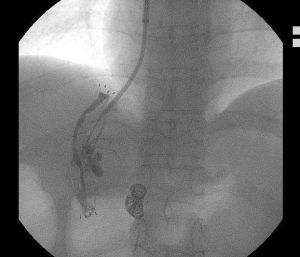

超聲精囊穿刺造影術系由參與國家“863”和“973”課題研究的名老專家聯合研發,在經直腸彩色B超引導下進行精囊穿刺,對所提取的抽取物進行病理化驗,無縫式診斷精囊、輸精管、射精管病變。結合中西藥精粹,通過軟絲輸送藥物離子直達病變部位,對梗阻性無精症可起到迅速復通的作用。相對傳統的造影術,超聲精囊穿刺造影術無需開刀,無疼痛,最快5分鐘即可完成整個診療過程,為臨床男性不育症提供了新型、可靠的診療方法,被譽為梗阻性無精症診療的金標準。

超聲精囊穿刺造影術改變傳統造影術需開刀、容易造成新損傷的弊端,全程微創、無痛診療,只需一根軟絲即可診斷是否精囊、輸精管、射精管病變,並可直接輸送藥物離子直達病變部位,最大程度避免損傷,達到快速復通梗阻的效果。